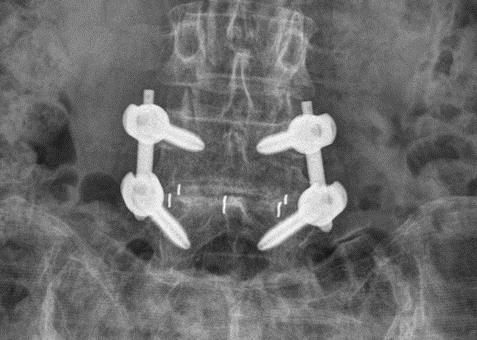

요추 척추체간 유합술은 두 개 이상의 인접한 요추 사이의 뼈 유합을 달성하는 것을 목표로 하는 수술 방법입니다. 이 수술에는 추간판을 제거하고 뼈 이식재 또는 뼈 이식 재료로 채워져 있는 케이지(cage)라 불리는 스페이서(spacer)로 교체하는 과정이 포함됩니다. 또한 이식된 뼈가 어긋나거나 벗어나지 않도록 척추체를 고정시키는 척추경 나사 고정술 방법까지 포함됩니다. 시간이 지남에 따라 척추뼈가 서로 유합되면, 해당 분절은 움직임이 사라집니다.

후방 요추체간 유합 (Posterior lumbar interbody fusion, PLIF): 등(후방)에서 실시되며 척추에 직접 접근할 수 있지만 더 많은 근육 손상이 수반될 수 있습니다.

경추간공 요추체간 유합술(Transforaminal lumbar interbody fusion, TLIF): PLIF의 변형으로 디스크 공간에 대한 측면 접근 방식을 제공하여 더 많은 뼈와 인대 구조를 보존합니다.